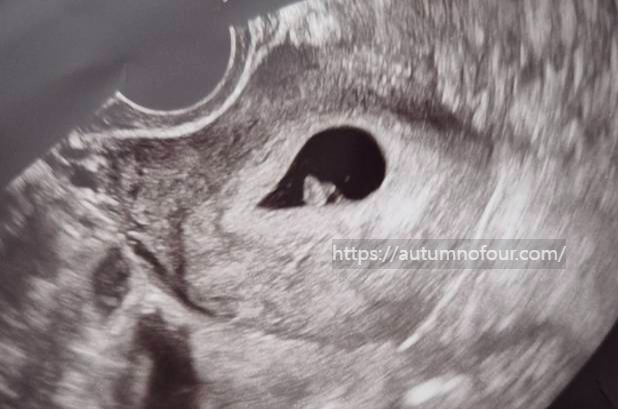

3. 초음파 확인

오늘도 역시나 진료실에 들어가자마자 초음파실로 향했다.

아기집을 본 이후로는 뭔가 초음파 볼 때 두근두근 하는 것 같다.

잘 자랐으려나.

옷을 갈아 입고 나오니

진료실 책상에 보이는 초음파 사진들!

지난주엔 없던 무언가가 아기집 안에 생겼다.

신기신기! 왕신기!

아직 아가는 아주 작지만, 난황이 아주 예쁘게 있어서 한결 마음이 편해졌다

피비침도 초음파상 문제가 없어서 괜찮을거라고

원장선생님이 대수롭지 않게 얘기해주셔서 오히려 안심이 되었다.